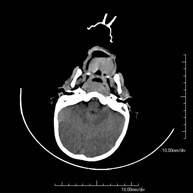

- Skull CT

Radiological test that provides high definition anatomical images of the skull (brain stem, cerebellum, cerebrum, cranial calotte, etc.) using CT (Computed Tomography) equipment. Indicated for: trauma, headache, memory disorders, sudden loss of strength in a limb or half of the body.